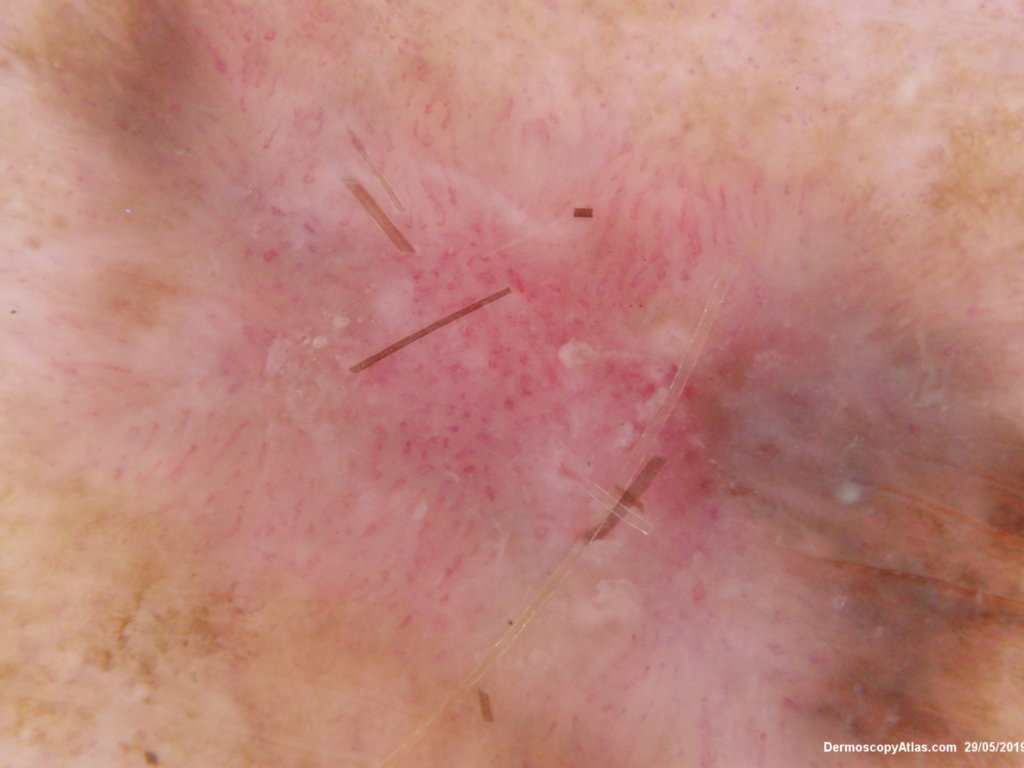

Image Number #3479 (Melanoma invasive)

Diagnosis: Melanoma invasive

Type: Dermlite Polarised

Pigmented lesion on the lower leg noted at an annual skin check. The clinical is suggestive of a melanoma but the dermatoscopy was initially interpreted as coiled vessels with lines radial peripheral of an IEC. In IEC the lines radial are usually made up of dots but these are solid streaks. There is some vessel variability in the pink area.

This was an invasive melanoma 0.4 mm thick but the histology shown shows mainly in situ melanoma.Have a look at the second case in the video below for a more detailed overview of the histology.